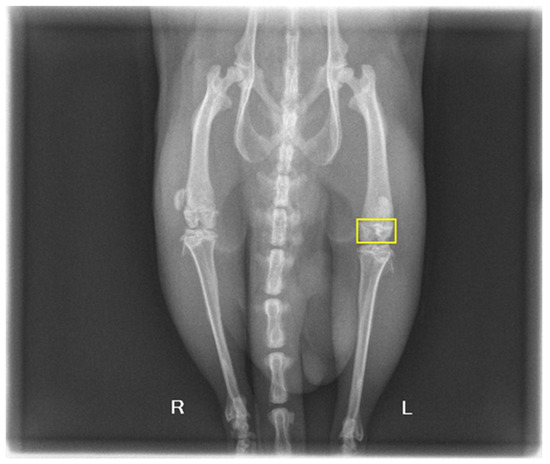

3.3. In Vivo Behavior of Biocomposites on Animals

- Ancuța, D.L.; Crivineanu, M.; Soare, T.; Coman, C. In vivo effects of titanium implants treated with biomaterials in the bone regeneration process. Sci. Works. Ser. C Vet. Med. 2021, LXVII, 155–160. [Google Scholar]

- Kokkinou, E.; Boniatis, I.; Costaridou, L.; Saridis, A.; Panagiotopoulos, E.; Panayiotakis, G. Monitoring of bone regeneration process by means of texture analysis. J. Instrum. 2009, 4, P09007. [Google Scholar] [CrossRef]

- MacKay, J.W.; Murray, P.J.; Low, S.B.L.; Kasmai, B.; Johnson, G.; Donell, S.T.; Toms, A.P. Quantitative analysis of tibial subchondral bone: Texture analysis outperforms conventional trabecular microarchitecture analysis. J. Magn. Reson. Imaging 2016, 43, 1159–1170. [Google Scholar] [CrossRef]